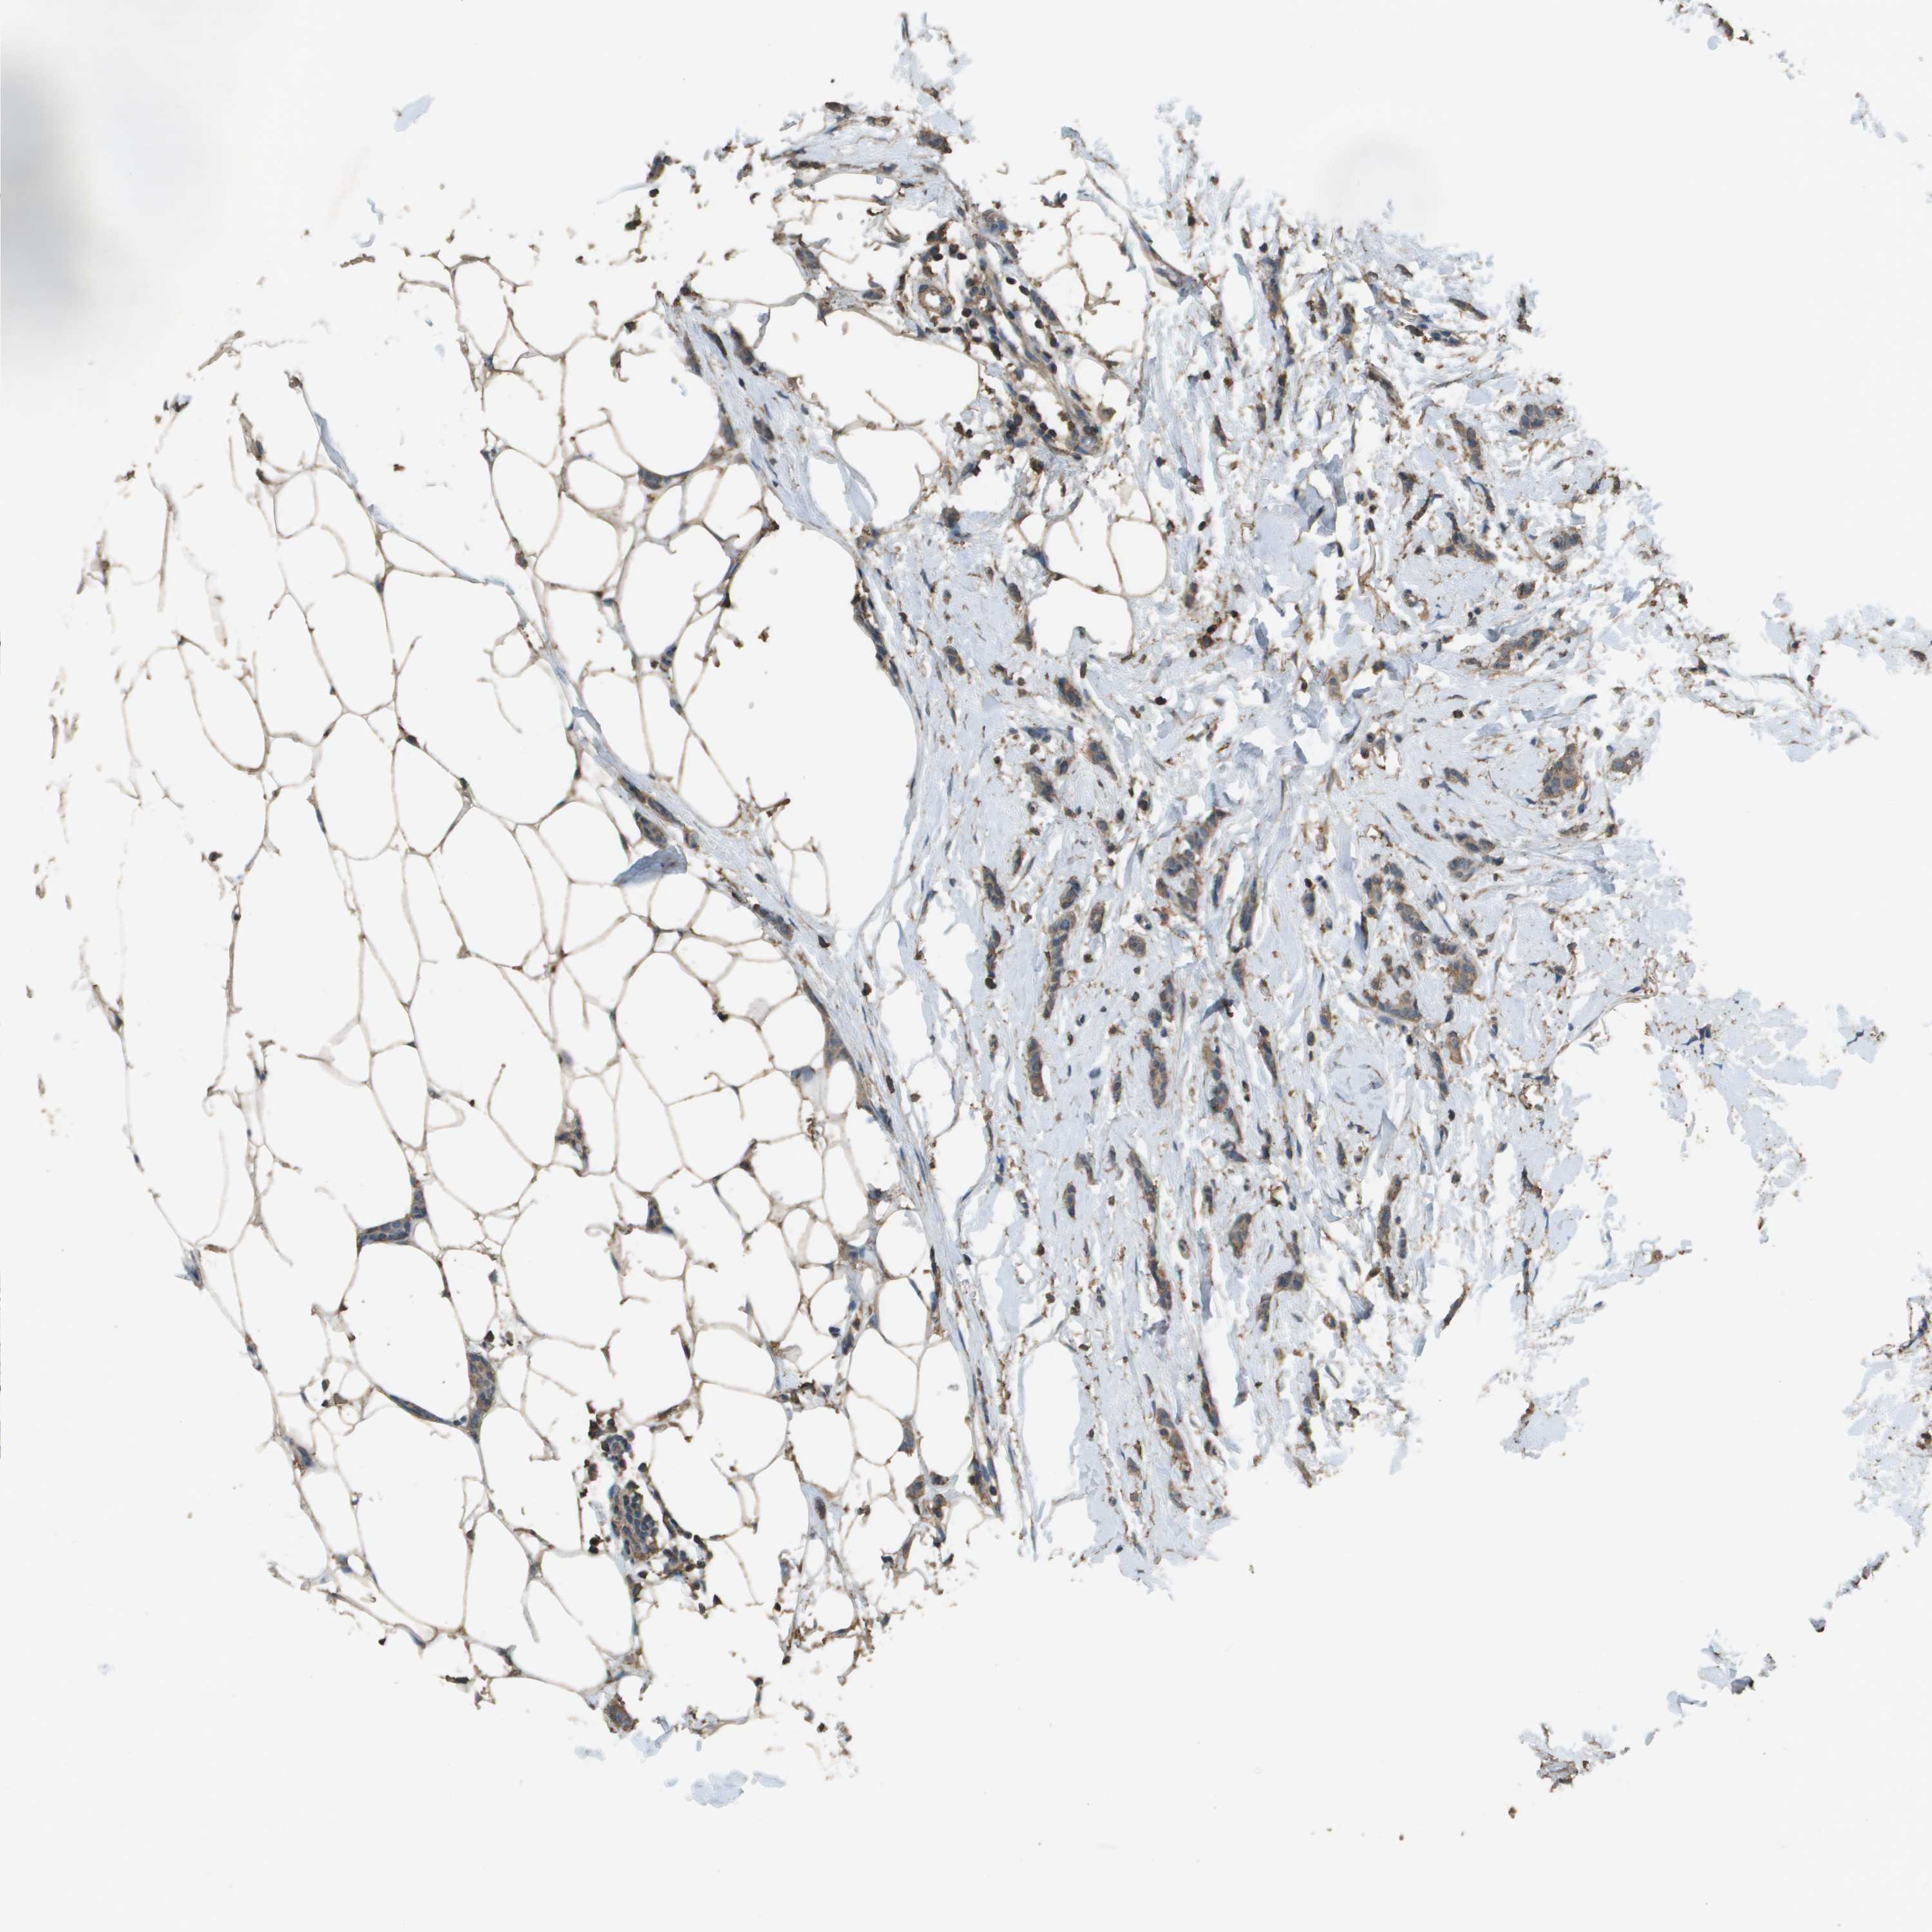

CANCER BREAST CANCER Show tissue menu

BRCA TCGA BRCA VALIDATION PROTEIN EXPRESSION

Breast cancer

Human cancer